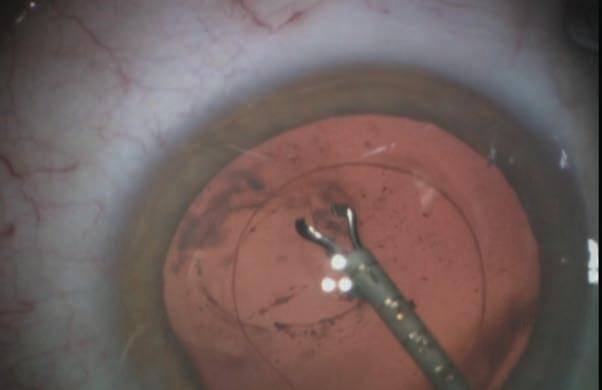

Figure 1: OVD is injected into the capsular bag to create tension on the edges of the posterior capsular tear. The posterior polar opacity is seen at the left edge of the opening.

Figure 2: MST-Seibel capsule forceps grasp the edge of the posterior capsular defect to initiate the posterior capsulorhexis.